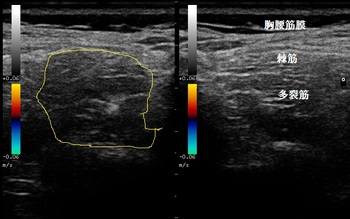

右大腿部 超音波長軸像 右同部 短軸像

超音波検査をしたところ、中間広筋が打撲により挫滅し内出血と浮腫が認められました(左右画像の

赤丸内)。